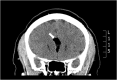

Figure 3

Brain CT—coronal plane, white arrow shows a large, well-defined low-density lesion involving the genu and body of the corpus callosum.